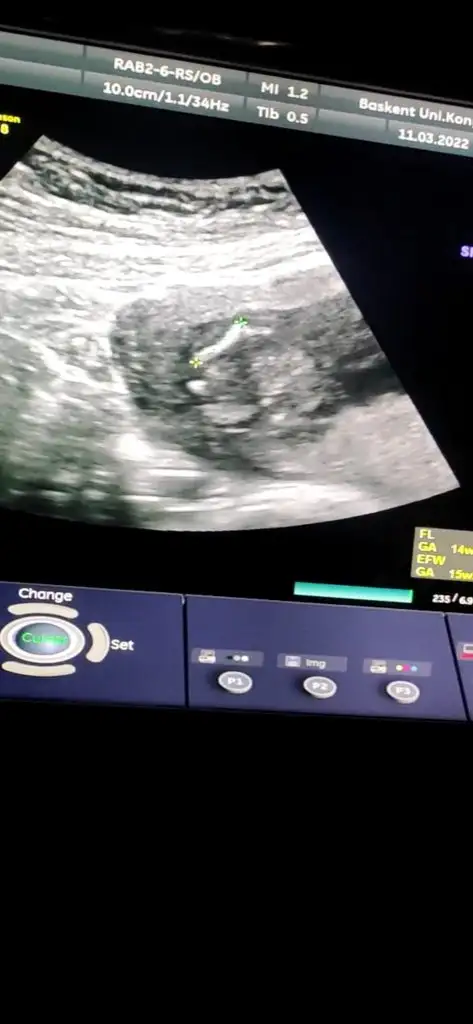

Ben bişey anlayamadım nuba göre benim ne oluyor acabaCumartesi cinsiyet öğreneceğim o yüzden bütün teorileri araştırırken bu karşıma çıktı bana mantıklı geldi gibişöyle ki omurgadan popoya doğru giden çizgi sonda yukarı doğru çıkıyorsa erkek, düz gidiyorsa kız oluyormuş fotoğraf ekleyeceğim orda daha ayrıntılı gösteriyor

Dr da öyle dedi emin olamadı alttan bakınca da kıza benziyor dediAyy maşallah ne güzel çıkmışsanki şu işaretlediğim yerde yukarı doğru bir çıkıntı varmış gibi geldi bana Öyle olunca da erkek deniyor ama bilemiyorum tamamen benim yorumum